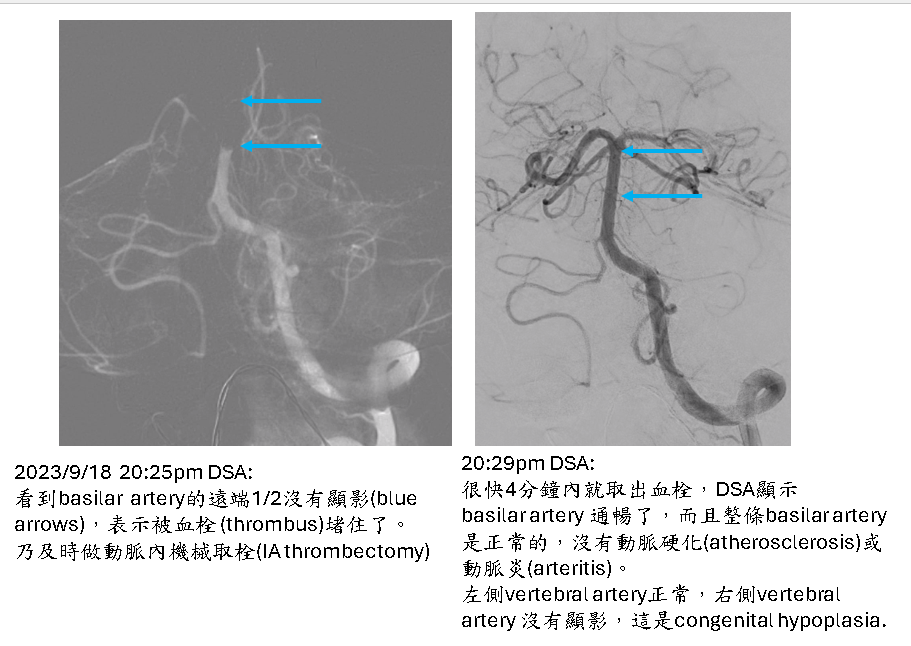

Acute pontine infarction, both sides of pons, with hemorrhagic transformation in left side, due to thrombosis in the parent artery (distal 1/2 of basilar artery )

這不是典型的pontine lacunar infarction due to small vessel disease.

這是pons的母血管basilar artery血栓(thrombus)堵住所引起,算是一種embolism (thromboembolism).

至於這血栓(thrombus)是如何形成的? 已查過heart, aorta, 都沒問題,所以不是cardiogenic。

Vertebro-basilar system也無atherosclerosis or arteritis 這些容易就地血栓形成(in situ thrombosis)的血管疾病。